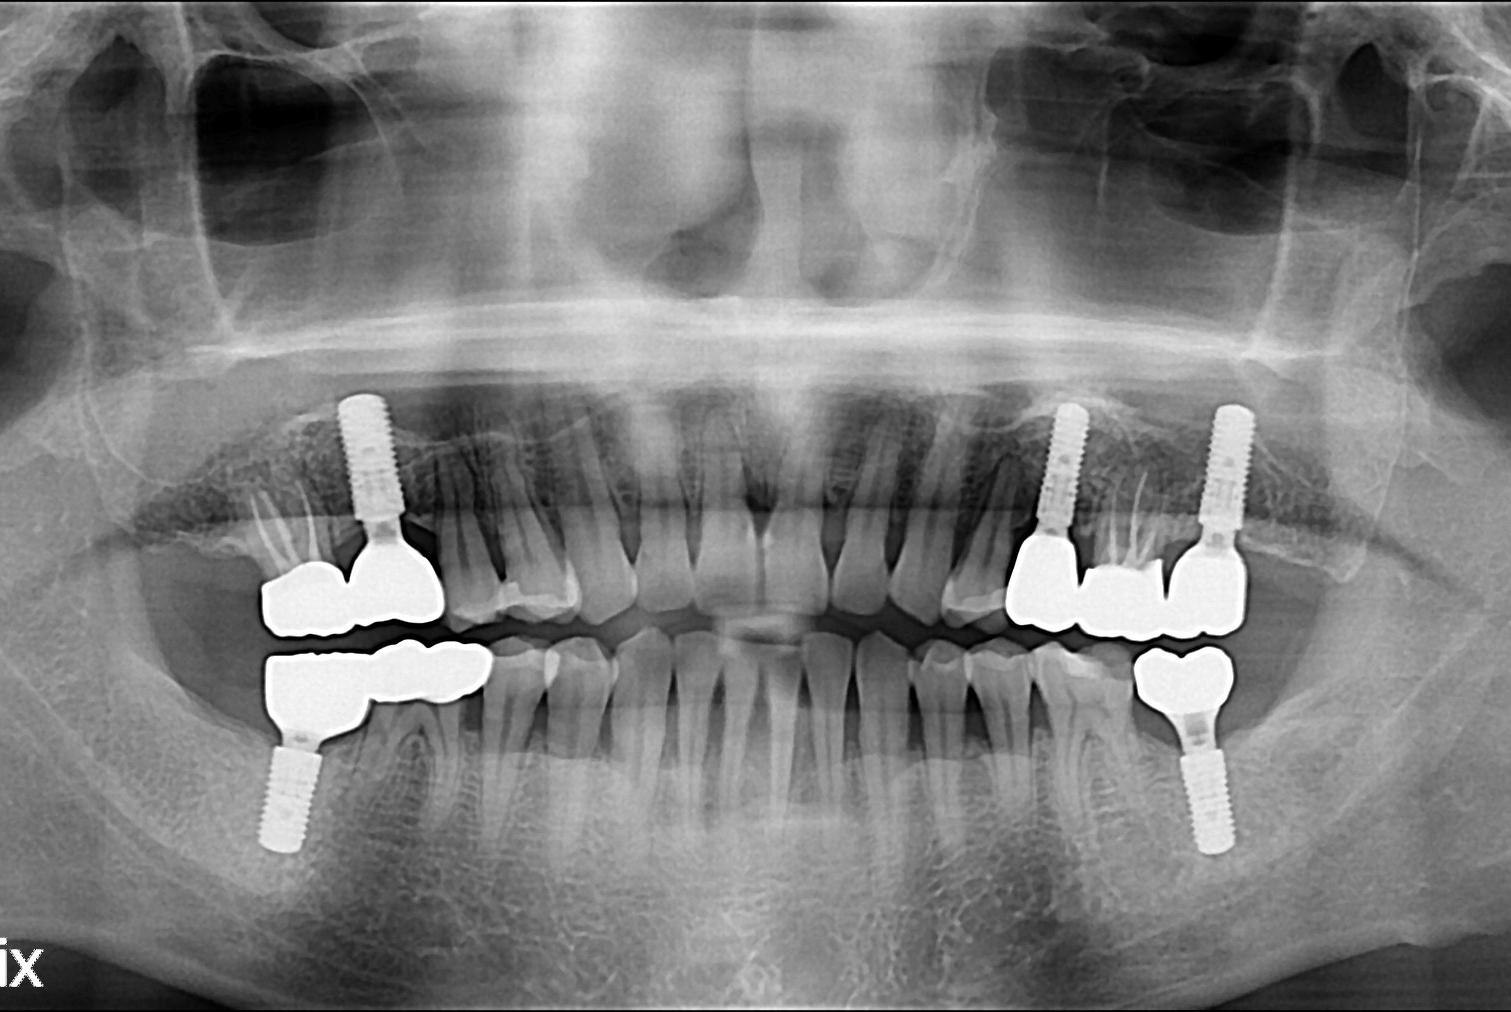

[임플란트] 임플란트

치료후 : 2019-08-30

세종치과는 많은 환자와 다양한 케이스를 바탕으로 항상 편안한 임플란트 수술을 제공하고자 노력하고,

오래동안 튼튼히 쓸 수 있는 임플란트 수술을 가장 큰 목표로 삼고 있습니다